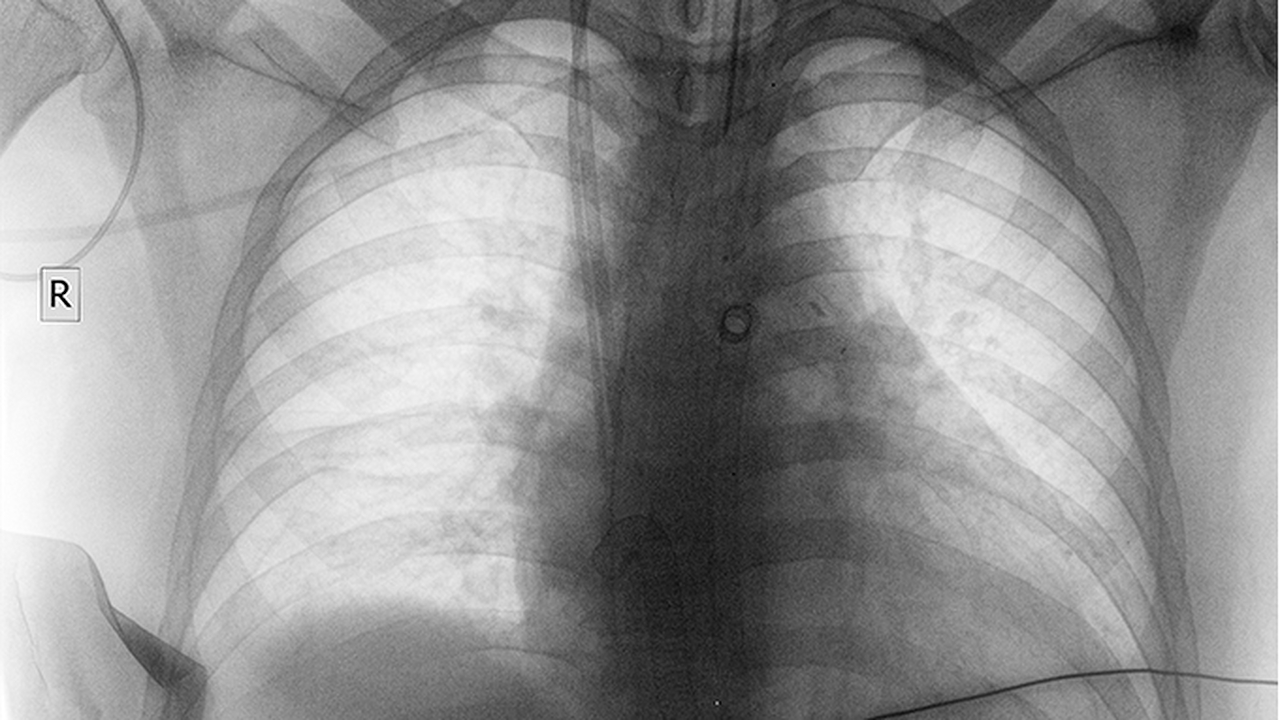

山东省肿瘤医院是山东省规模大的三级甲等肿瘤专科医院,在肺癌诊疗领域处于省内地位。医院拥有完善的肺癌多学科诊疗团队,配备PET-CT、达芬奇手术机器人等设备。医院开展肺癌的早期筛查、诊断、微创手术、放疗、靶向治疗等综合治疗手段,年肺癌手术量超过2000例。医院参与多项肺癌临床研究项目,在肺癌个体化治疗方面积累了丰富经验。医院还设有肺癌筛查中心,为高危人群提供低剂量螺旋CT筛查服务。

山东大学齐鲁医院是山东省综合实力强的三级甲等医院之一,其胸外科和肿瘤科在肺癌诊疗方面具有突出优势。医院拥有山东省重点实验室和多个临床医学研究中心,开展肺癌的早期诊断和综合治疗。医院配备有3.0T磁共振、256排螺旋CT等高端影像设备,能够实现肺癌的诊断。在治疗方面,医院常规开展胸腔镜肺癌术、机器人辅助肺癌手术等微创技术,同时开展基因检测指导下的靶向治疗和免疫治疗。医院还设有肺癌多学科会诊中心,为疑难病例提供个性化治疗方案。

山东省立医院是山东省首批三级甲等综合医院,其呼吸与危重症医学科和胸外科在肺癌诊疗方面具有丰富经验。医院拥有山东省呼吸疾病研究所和多个省级重点专科,开展肺癌的早期筛查和综合治疗。医院配备有电子支气管镜、超声支气管镜等设备,能够实现肺癌的诊断和分期。在治疗方面,医院常规开展胸腔镜肺癌手术、射频消融等微创治疗技术,同时开展化疗、靶向治疗和免疫治疗等综合治疗手段。医院还参与多项肺癌临床研究项目,为患者提供新的治疗方案。